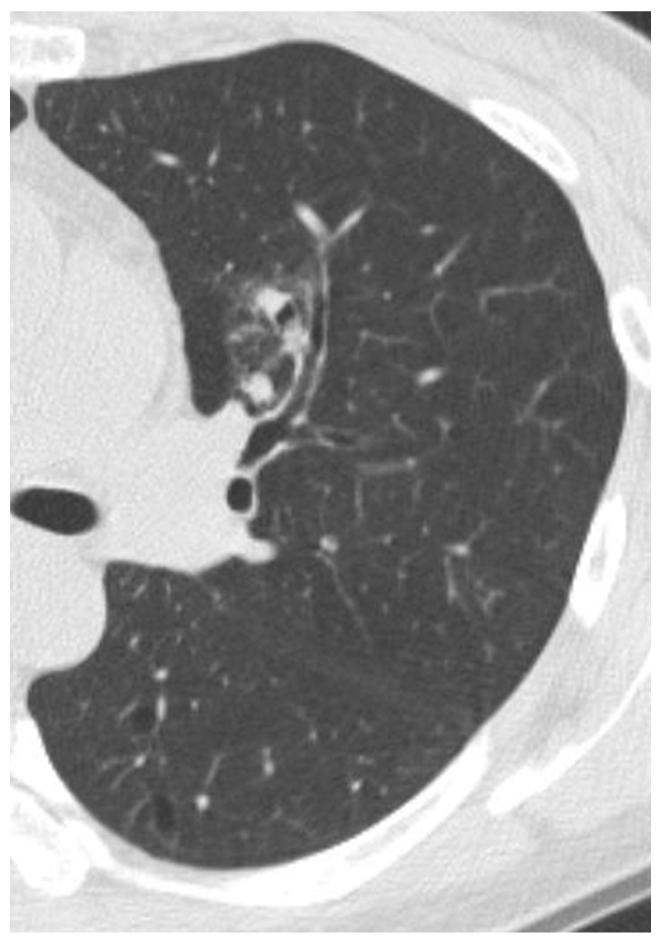

Ninety-six nodular GGOs in 55 individuals followed by CT for at least one month from an initial chest CT were included. Forty nodular GGOs in 30 individuals were pathologically confirmed to be: adenocarcinoma (n = 15), bronchioloalveolar carcinoma (BAC) (n = 11), atypical adenomatous hyperplasia (AAH) (n = 8), focal interstitial fibrosis (n = 5) and aspergillosis (n = 1). Lesions were categorized based on high-resolution CT findings: pure nodular GGO (PNGGO) < or = 10 mm, PNGGO > 10 mm, mixed nodular GGO (MNGGO) < or = 10 mm, and MNGGO > 10 mm. In each group, the change in size during the follow-up period, the pathological results and the rate of malignancy were evaluated.

Three MNGGO lesions, and none of the PNGGO, grew during the follow-up period. Resected PNGGOs < or = 10 mm were AAH (n = 6), BAC (n = 5), and focal interstitial fibrosis (n = 1). Resected PNGGOs > 10 mm were focal interstitial fibrosis (n = 4), AAH (n = 2), BAC (n = 2), and adenocarcinoma (n = 2). Resected MNGGOs < or = 10 mm were adenocarcinoma (n = 2), and BAC (n = 1). Resected MNGGOs > 10 mm were adenocarcinoma (n = 11), BAC (n = 3), and aspergillosis (n = 1).

Mixed nodular GGOs (MNGGOs) had the potential for growth; most were pathologically adenocarcinoma or BAC. By contrast, PNGGOs were stable for several months to years; most were AAH, BAC, or focal interstitial fibrosis.